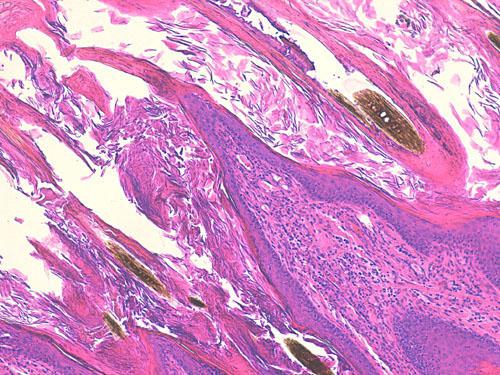

Photo 11 (Hémalun Eosine X 100): l’épiderme et les infundibula folliculaires

sont hyperplasiques et hyperkératosiques. Notez la projection papillaire à la marge d’un ostium folliculaire.

Le derme montre une inflammation péri-vasculaire.

Légendes de la Photo 11 :

- Flèche turquoise : projection papillaire de l’épiderme hyperplasique se formant à la marge d’un ostium folliculaire

- Ronds marrons : tiges pilaires

- Ovales turquoises vides : follicules pileux, infundibula hyperkératosiques (orthokératose)

- Double flèche orange : épiderme (portion non kératinisée)

- Double flèche verte : derme

- Étoiles rouges : infiltrat inflammatoire dermique péri-vasculaire